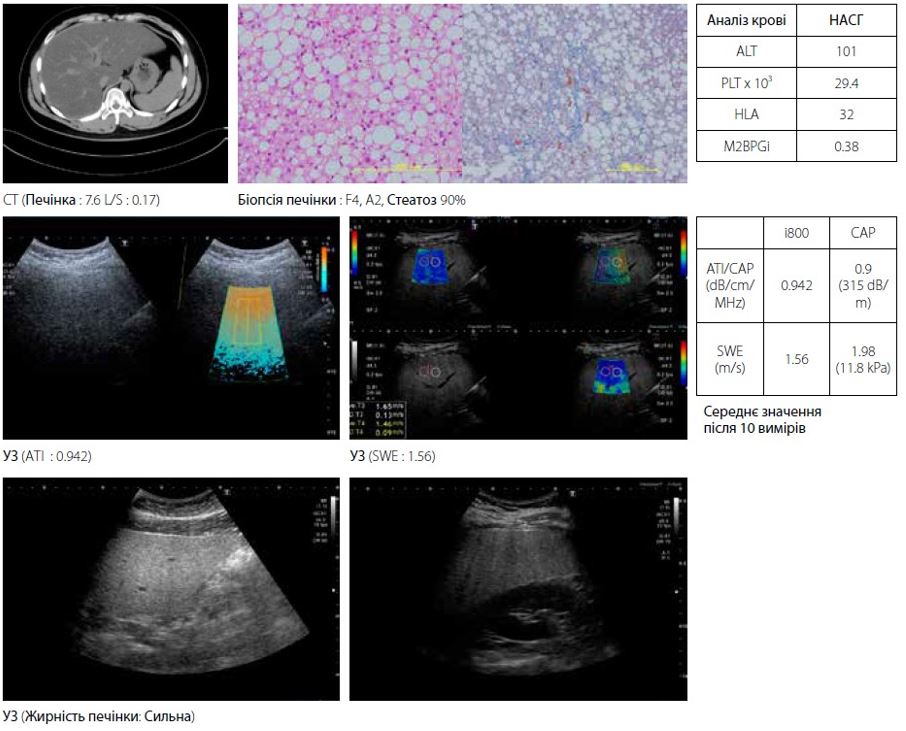

Нижче наведено 2 клінічних випадки з НАСГ.

Чоловікові близько 20 років з діагнозом НАСГ при виразковому коліті (рис. 6). КТ співвідношення L/S підтвердило стеатоз. У B-режимі крапчастий малюнок паренхіми печінки не вказує на фіброз, однак початок фіброзу можна підтвердити на основі очевидного підвищення АЛТ (101 МО/л) і PLT (290 000/мкл) у аналізі крові та результатах гістології. І еластографія зсувної хвилі (1,56 м/с), і FibroScan (1,98 м/с) демонструють високе значення жорсткості печінки. Якщо рання терапія не буде проведена, прогнозується, що НАСГ переросте в цироз печінки до досягнення ним 40 років. У цьому типі випадків раннє виявлення проблеми є важливим для подальшої якості життя пацієнта.

Малюнок 6 Випадок 1: НАСГ при виразковому коліті